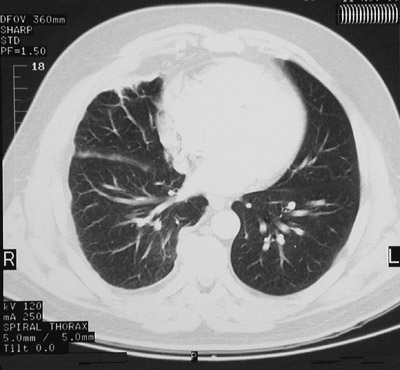

This chest CT scan in "lung window" demonstrates a mesothelioma involving the right pleura with thickening and nodularity. The neoplasm is seen near the base of the lung above and the upper lung below.